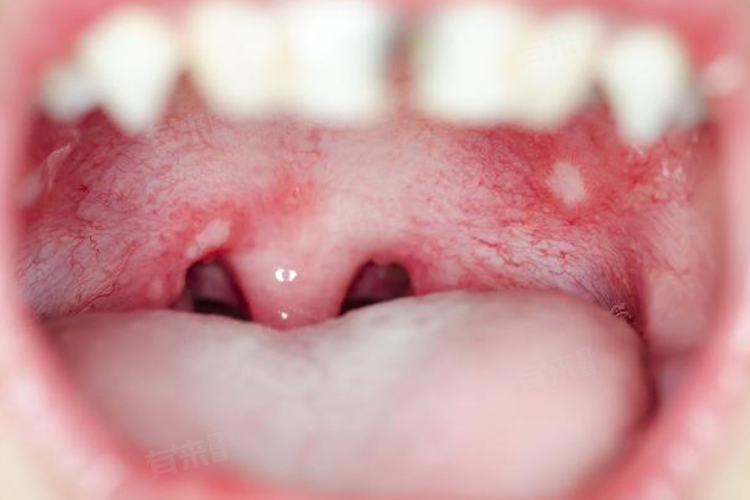

2、感染:口腔卫生不良,细菌、病毒等微生物感染可导致上腭炎症,如疱疹性口炎,由单纯疱疹病毒引起,在上腭可出现成簇的小水疱,破溃后形成溃疡,产生疼痛。念珠菌感染也可能发生在上腭,表现为黏膜发红、疼痛,可见白色斑膜。注意口腔清洁,用淡盐水漱口。